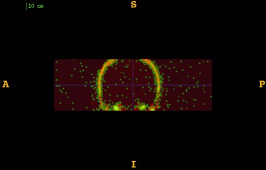

Figure 1 shows the examples of pixel selection masks generated using tested approaches at the highest resolution level for pixel sampling rate 0.5%. It is obvious that the samples generated with the URS approach are extremely spread, whereas the samples generated with the GMS approach are overly concentrated along the gradient magnitude structures present in the image. The proposed approach produces samples that balance those two extremities.